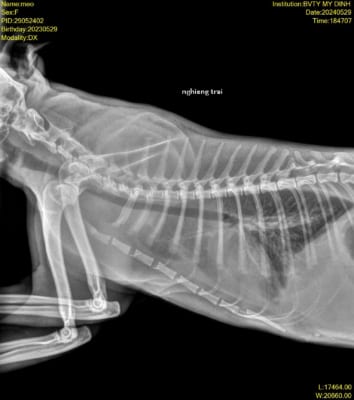

Theo dõi sát sao là chìa khóa: khám lại thường xuyên, chụp X-quang mỗi 2 tuần để kiểm tra tiến triển. Giữ môi trường sạch sẽ, ấm áp, và kiên nhẫn vì hồi phục có thể mất vài tuần. Với sự chăm sóc đúng cách, mèo yêu của bạn sẽ khỏe mạnh trở lại thôi!

Đừng quên khám sức khỏe định kỳ, chụp X-quang phổi nếu cần, phát hiện sớm là cứu cánh. Nếu nhà có mèo bệnh, cách ly ngay và khử khuẩn tay sau khi chăm sóc.